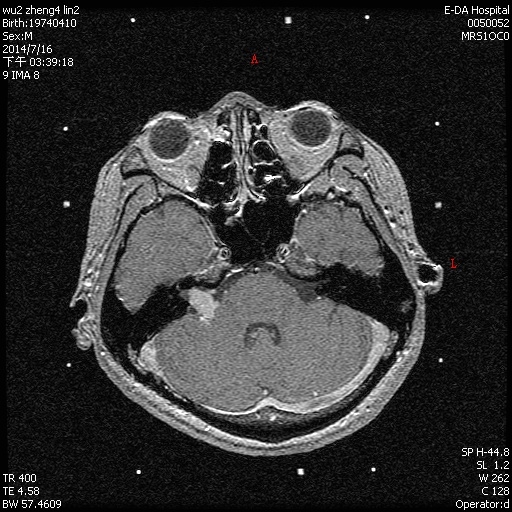

聽神經瘤

手術前

手術後